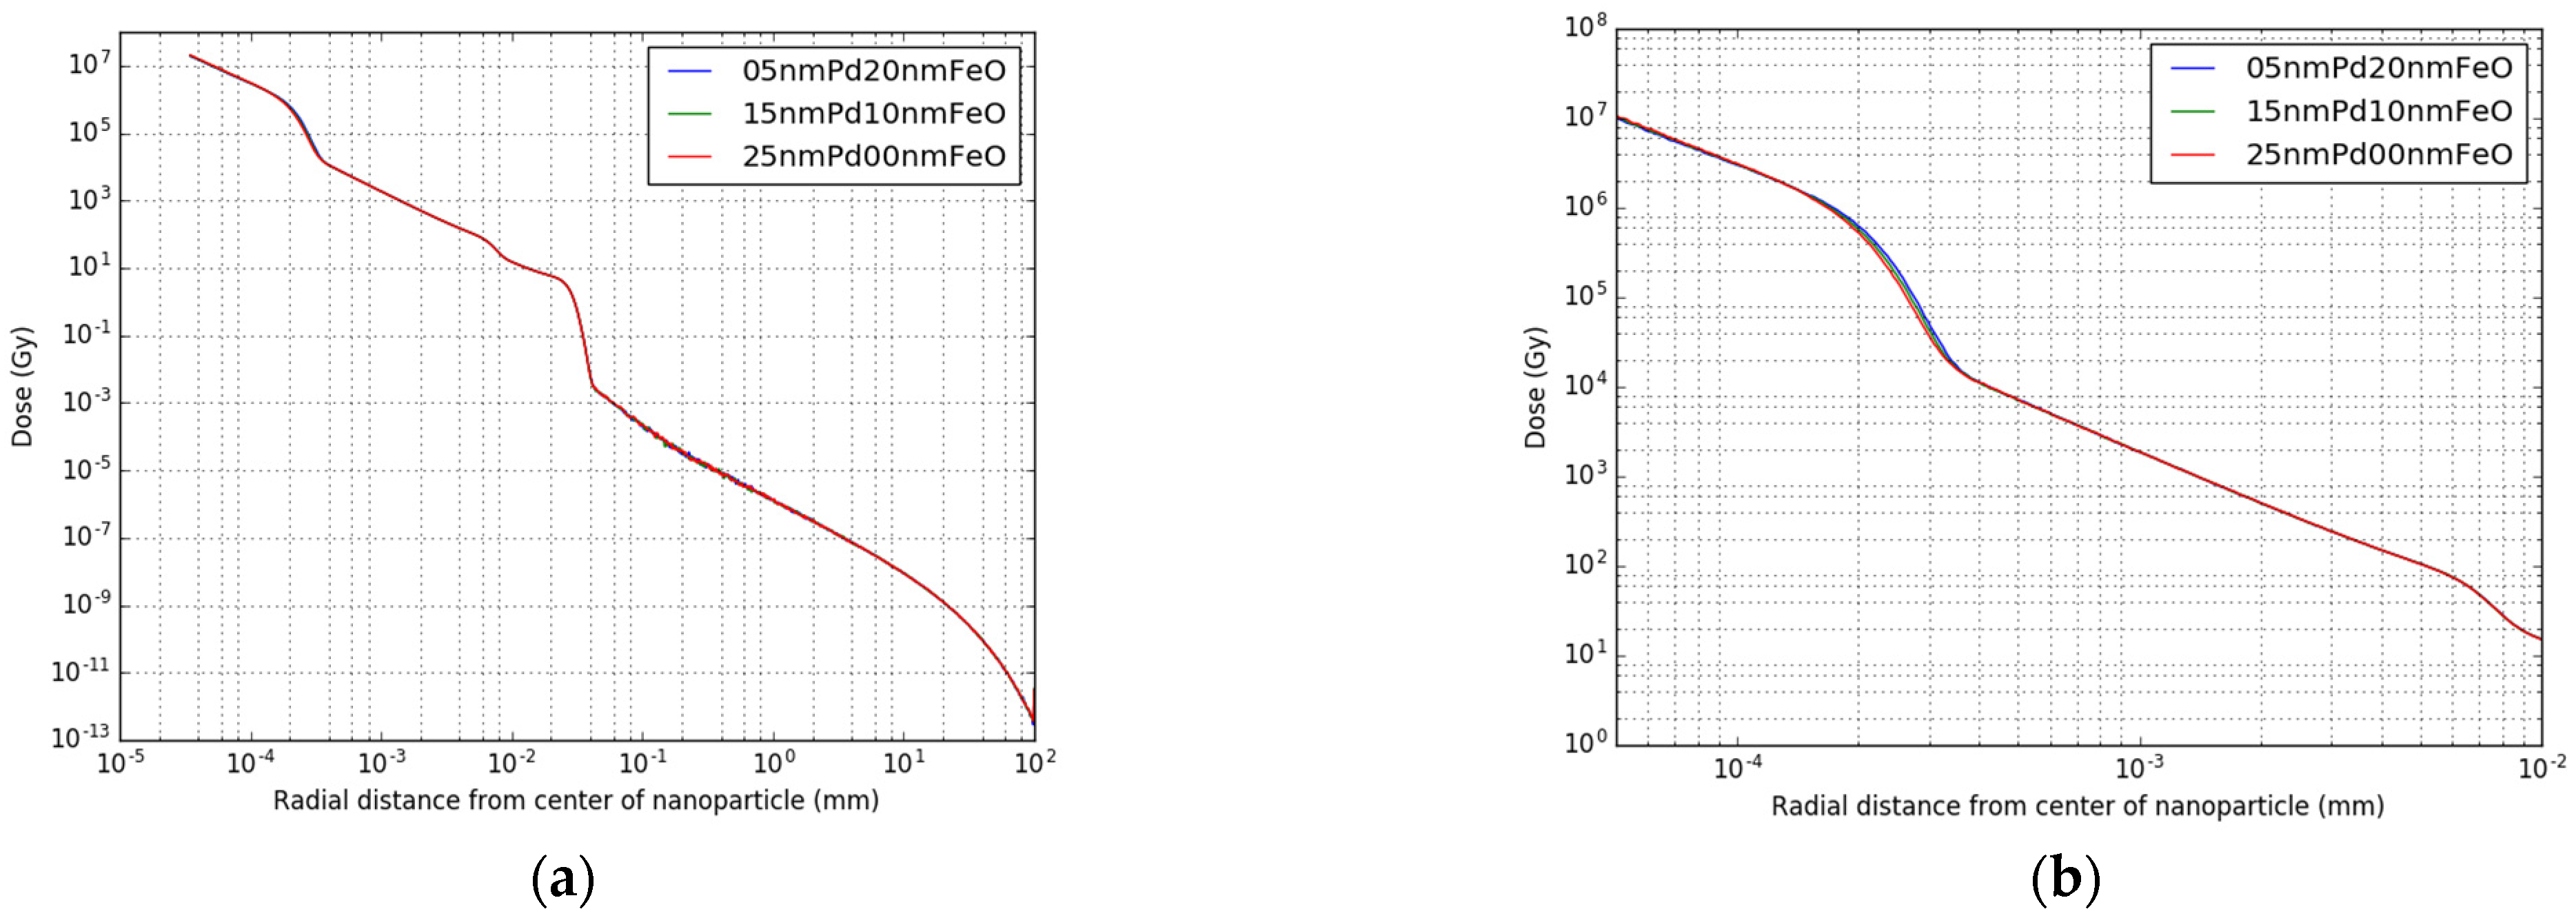

2.2. Single Nanoparticle Simulations

3.1. Single Nanoparticle Energy Spectra

3.2. Radioactive Magnetic Nanoparticle (RMNP) Seed